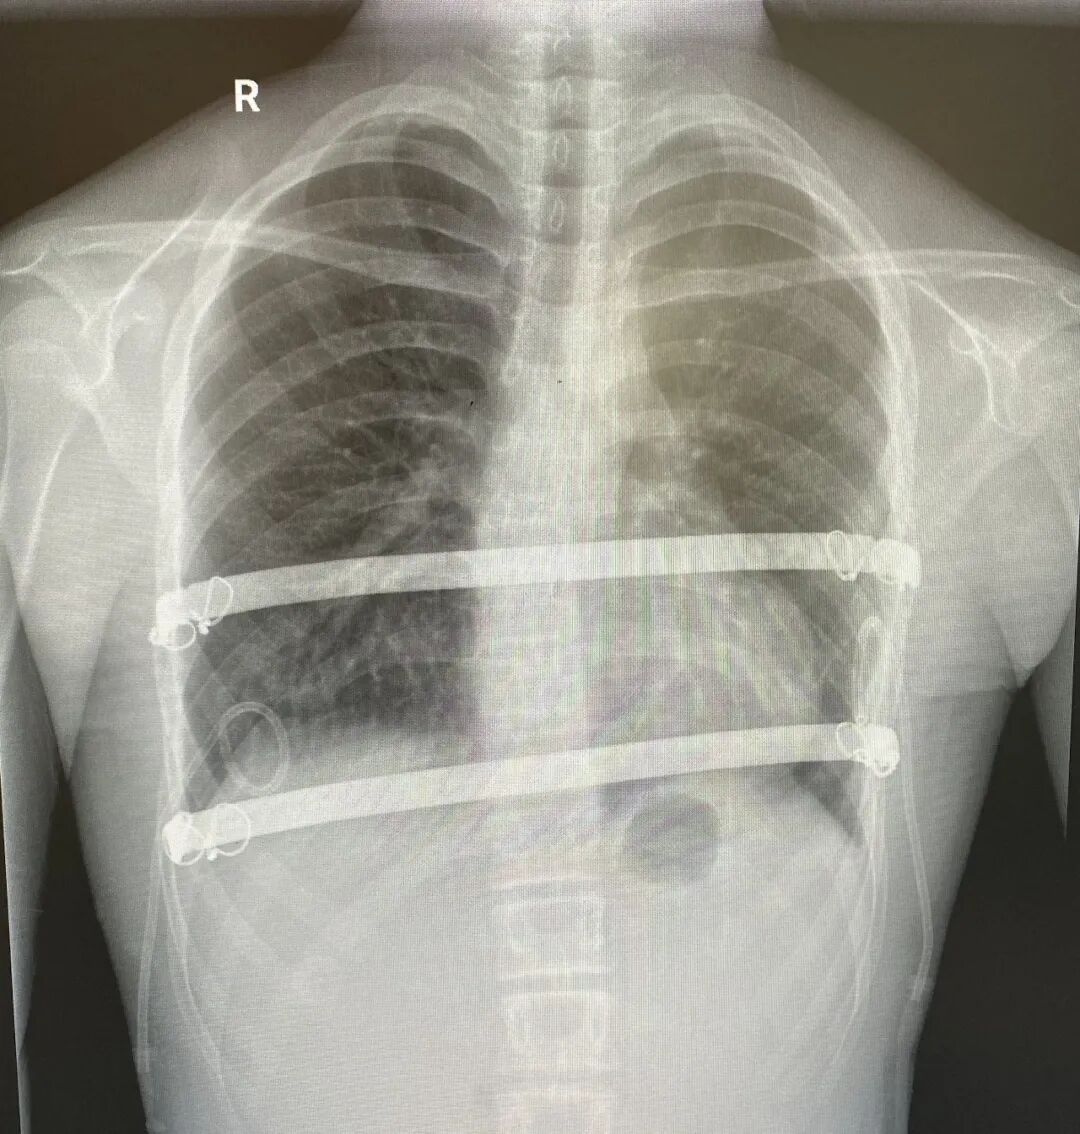

家人带着小宇找到漳州第三医院胸外科陈定柱副院长就诊。陈定柱副院长亲自主诊,统筹协调科室诊疗资源,指导诊疗团队开展全面评估为小宇进行了全面细致的体格检查,结合胸部 CT 检查结果,明确诊断为重度不对称漏斗胸——CT 报告显示,小宇的 Haller 指数约为 4.94。医学上,Haller 指数是评估漏斗胸严重程度的核心指标,正常人平均约为 2.52,指数>3.5 即可诊断为重度漏斗胸,小宇的指数已接近 5.0,意味着胸廓凹陷极其严重,心肺组织受到明显压迫,这也是其活动后胸闷气喘的根本原因。

手术过程中,胸外科团队在麻醉科与手术室团队的密切配合下,凭借精湛的手术操作技巧,精准分离组织、细致操作,成功将凹陷胸骨复位,彻底解除心肺组织压迫,精准重塑正常胸廓形态。整台手术过程平稳顺利,实现了创伤小、出血少的预期效果。